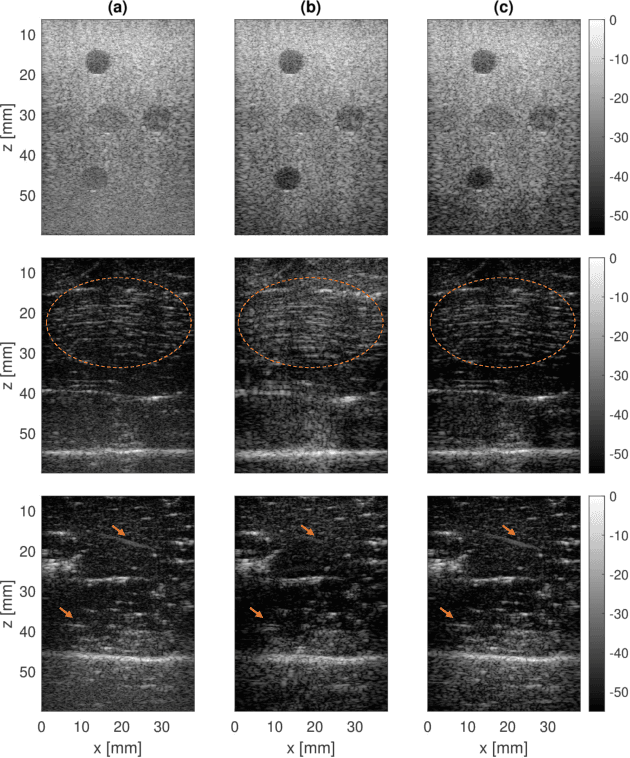

On one hand, the transmitted ultrasound beam gets attenuated as propagates through the tissue. On the other hand, the received Radio-Frequency (RF) data contains an additive Gaussian noise which is brought about by the acquisition card and the sensor noise. These two factors lead to a decreasing Signal to Noise Ratio (SNR) in the RF data with depth, effectively rendering deep regions of B-Mode images highly unreliable. There are three common approaches to mitigate this problem. First, increasing the power of transmitted beam which is limited by safety threshold. Averaging consecutive frames is the second option which not only reduces the framerate but also is not applicable for moving targets. And third, reducing the transmission frequency, which deteriorates spatial resolution. Many deep denoising techniques have been developed, but they often require clean data for training the model, which is usually only available in simulated images. Herein, a deep noise reduction approach is proposed which does not need clean training target. The model is constructed between noisy input-output pairs, and the training process interestingly converges to the clean image that is the average of noisy pairs. Experimental results on real phantom as well as ex vivo data confirm the efficacy of the proposed method for noise cancellation.